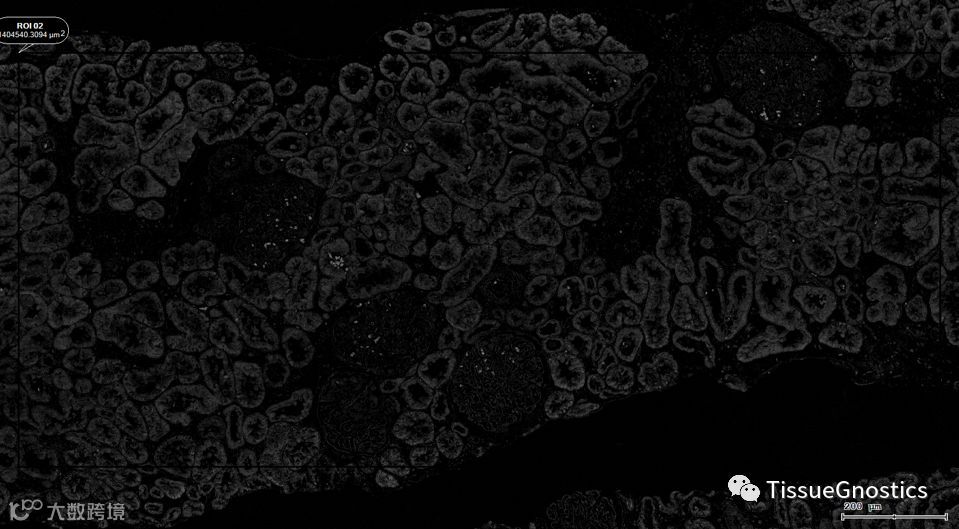

样本类型:PASM染色的肾脏活检样本

原始影像

银染通道分离